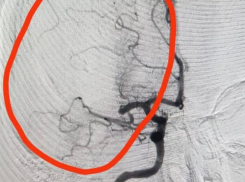

- Общество Тромб из головного мозга «вынули» волгоградские хирурги пациентке, которой неожиданно стало плохо 24.08.2023